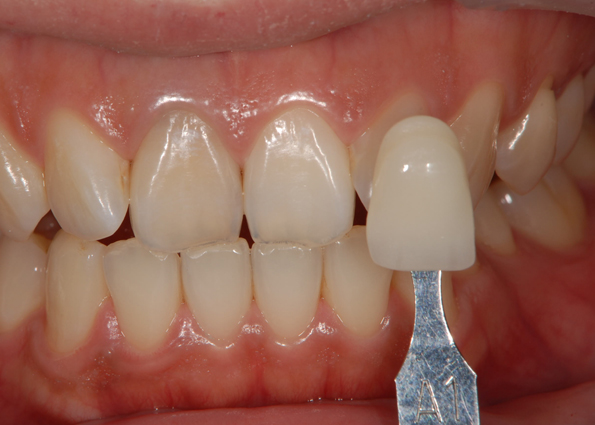

実際に色見本で確認していくと

神経を取った歯がA1まで変化していますが

神経をとってない歯が030 という色まで明るくなってきています。(A1よりも明るい色です)

神経を取ってある歯も、全体的に白くはなるのですが、周囲の歯に比べると、やはりどうしても神経を取ってある歯は反応が悪いです。